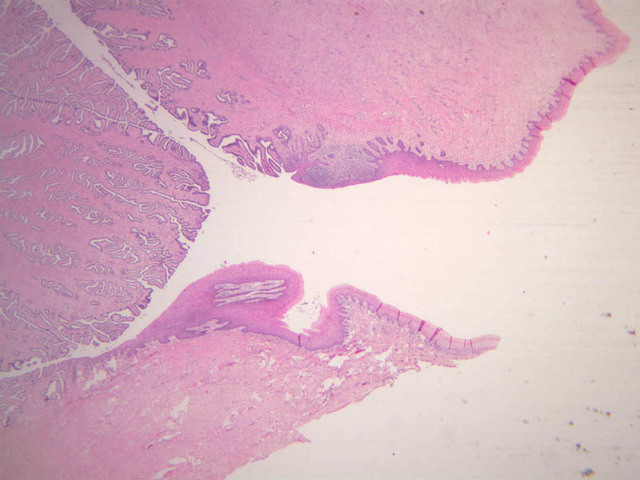

The endometrium of the cervical canal does not slough during the menstrual phase. The glands in this region are relatively large and extensively branched. They are lined by a tall simple columnar epithelium very active in the secretion of mucus. Occasionally these glands become blocked forming Nabothian cysts. The transition of the epithelium of the cervix to that of the vagina is abrupt and is in the region of the external os. At this point, the cervical simple columnar is replaced by the vaginal stratified squamous epithelium (slide B-98 [2.5x-labeled, 10x, 20x, 40x] [2.5x, 10x, 20x, 40x]). This is an area which is commonly inflamed as well as a primary location of cervical cancer.